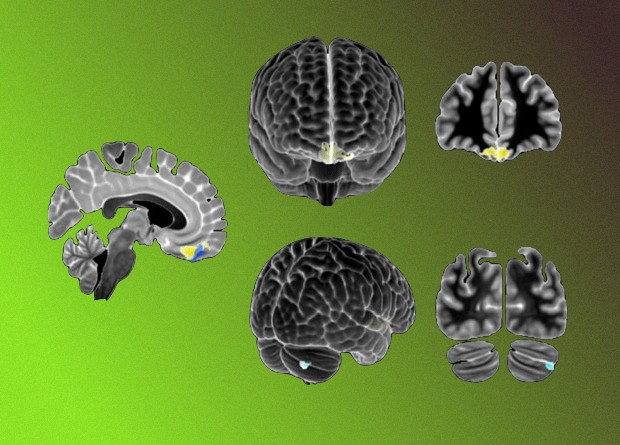

Нейрофизиологические основы РАС также до сих пор остаются малоизученными. Ряд исследований указывает на вклад мозжечковой дисфункции в развитие симптомов аутизма у мышей, в том числе из-за делеции гена Tsc1 в клетках Пуркинье. Во многихисследованиях были подробно описаны объемные изменения в задней части червя и в верхней полулунной дольке у детей с РАС; при этом они коррелировали и с тяжестью расстройства.

Питер Цай (Peter T. Tsai) с коллегами из Юго-западного медицинского центра Университета Техаса решили проверить, влияют ли нарушения активности мозжечка на работу медиальной префронтальной коры — участка мозга, который руководит когнитивными функциями у мышей с мутацией гена Tsc1 в клетках Пуркинье. Ученые предположили, что у таких мышей связь между верхней полулунной долькой мозжечка и левой прелимбической областью медиальной префронтальной коры может быть нарушена.